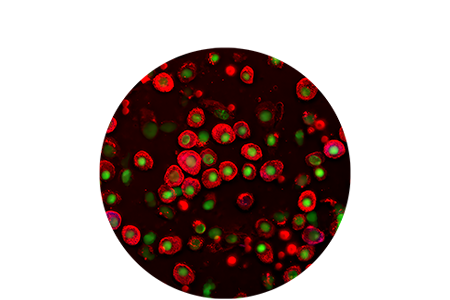

A microscopic view of blood cells.

La morfologia ematologica e la citologia automatizzate, in tempo reale, dell'analizzatore cellulare IDEXX inVue Dx forniscono risultati con la stessa accuratezza dei laboratori di riferimento entro 10 minuti. La procedura senza allestimento manuale del campione garantisce coerenza e accuratezza senza dover ricorrere al processo di preparazione dello stesso. L'analisi multidimensionale delle cellule combinata con lunghezze d’onda di luce e di fluorescenza multiple illuminano i singoli elementi cellulari, fornendo più informazioni diagnostiche rispetto ai metodi tradizionali con allestimento su vetrino.

Graphic of morphology cells.

Morfologia ematologica

Analisi automatizzata dei parametri morfologici, tra cui:

• piastrine anche in presenza di aggregati

• sferociti

• agglutinazione dei globuli rossi

• neutrofili immaturi

Integrata con i risultati degli analizzatori per ematologia ProCyte One e ProCyte Dx.